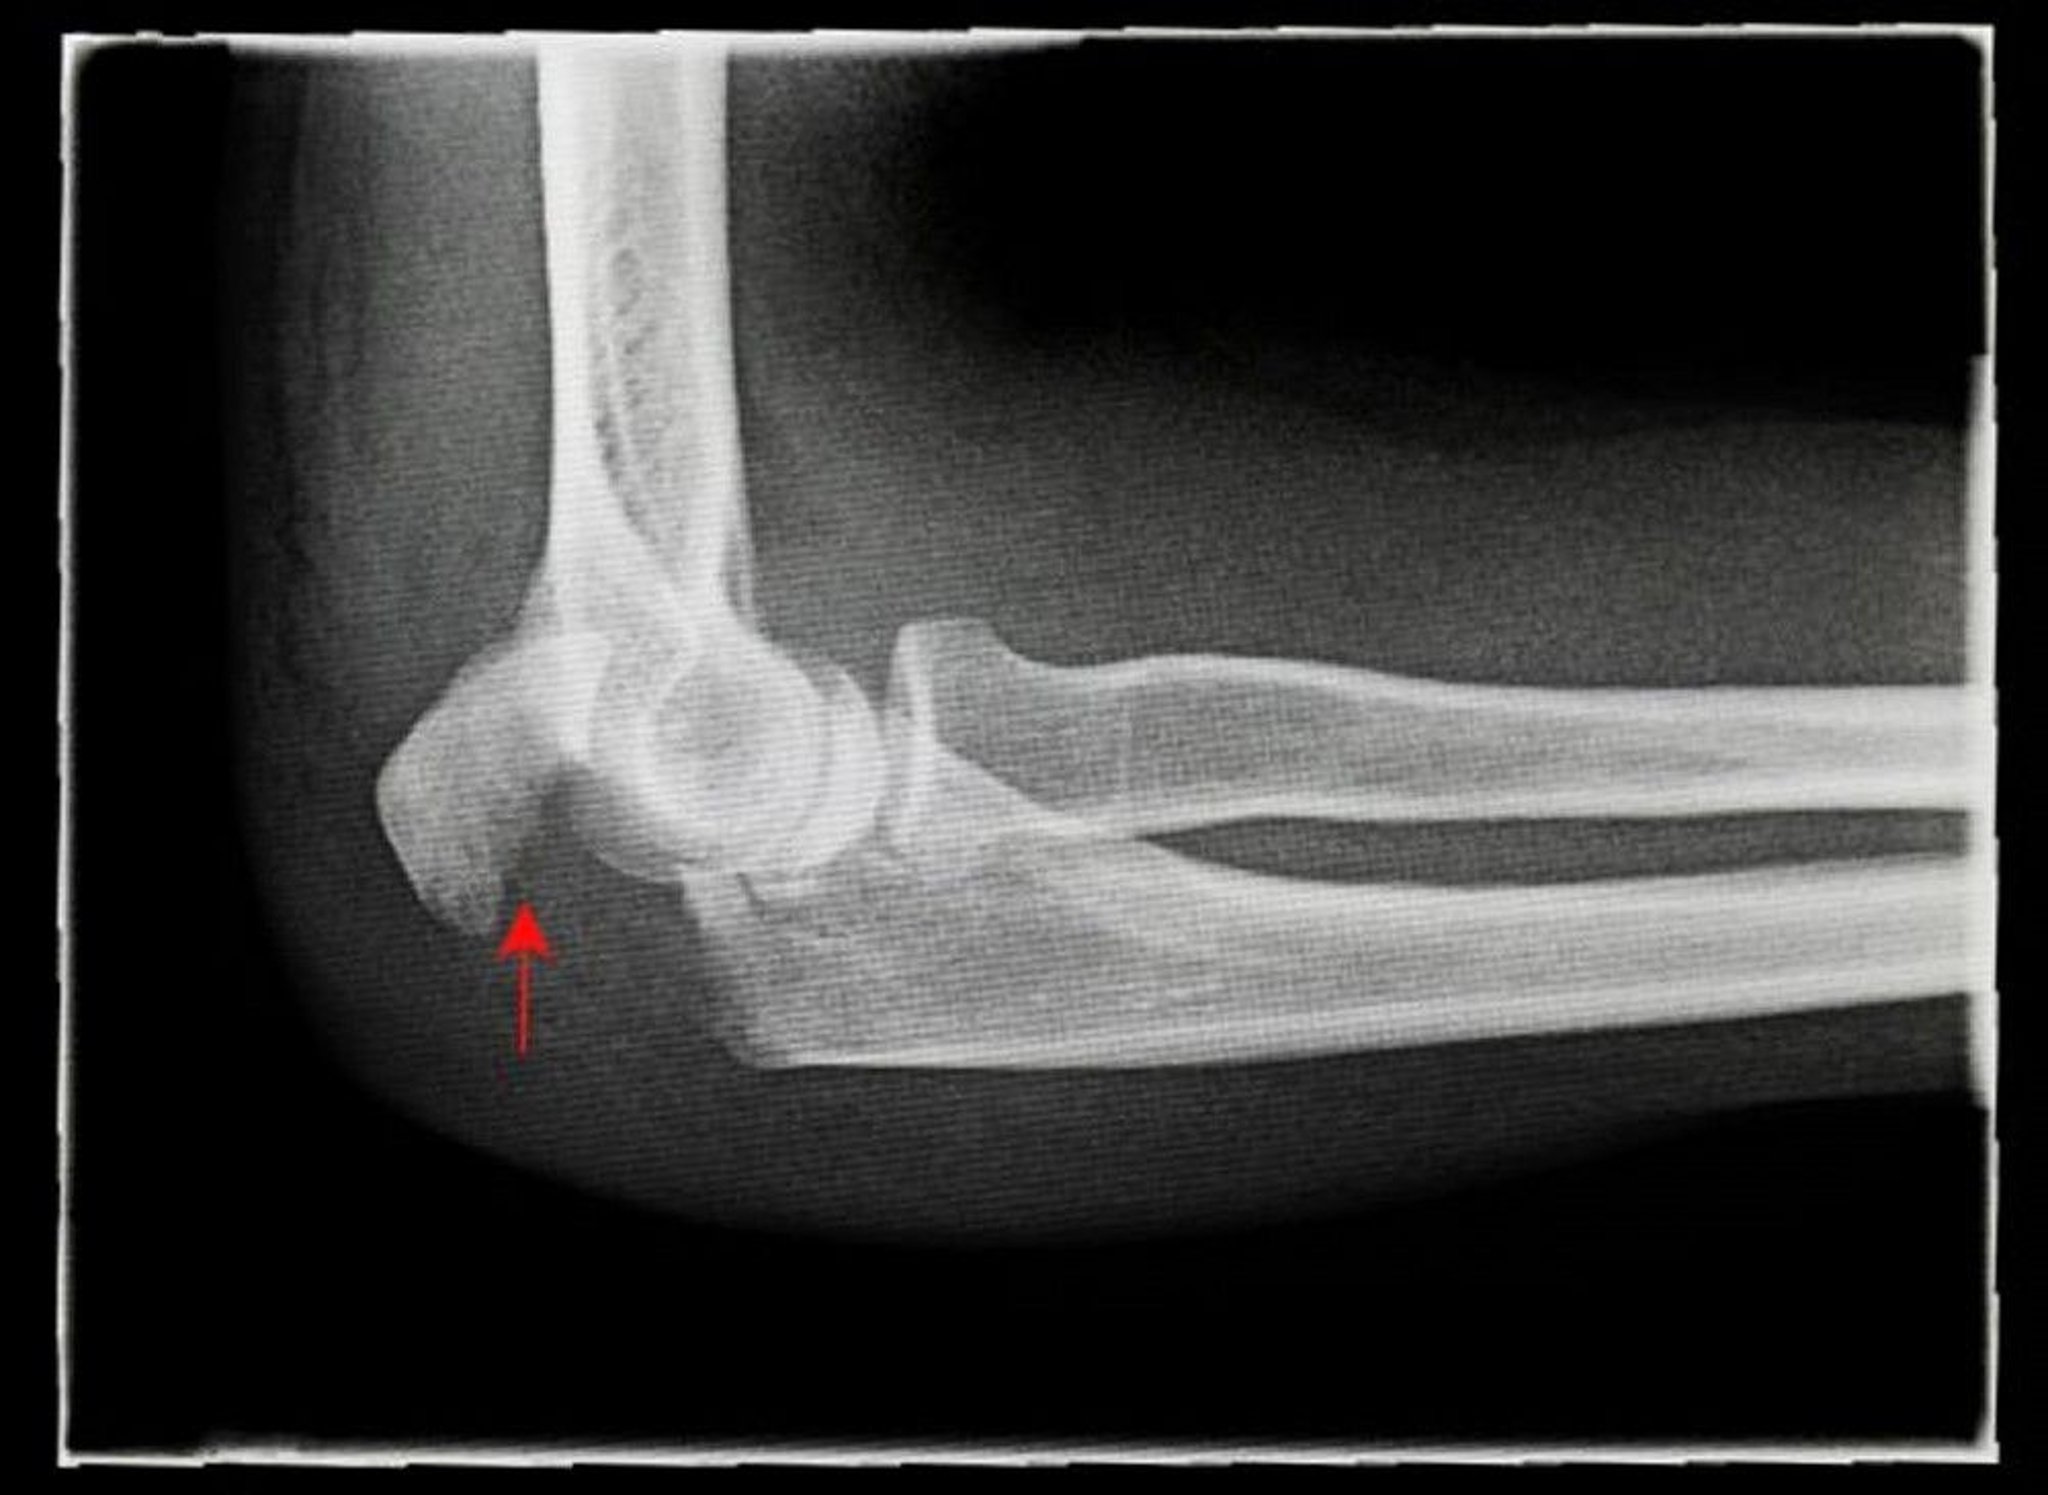

Fraktur Olekranon yang Bergeser

Foto sinar-x ini menunjukkan tampilan samping (lateral) fraktur olekranon yang bergeser (panah).